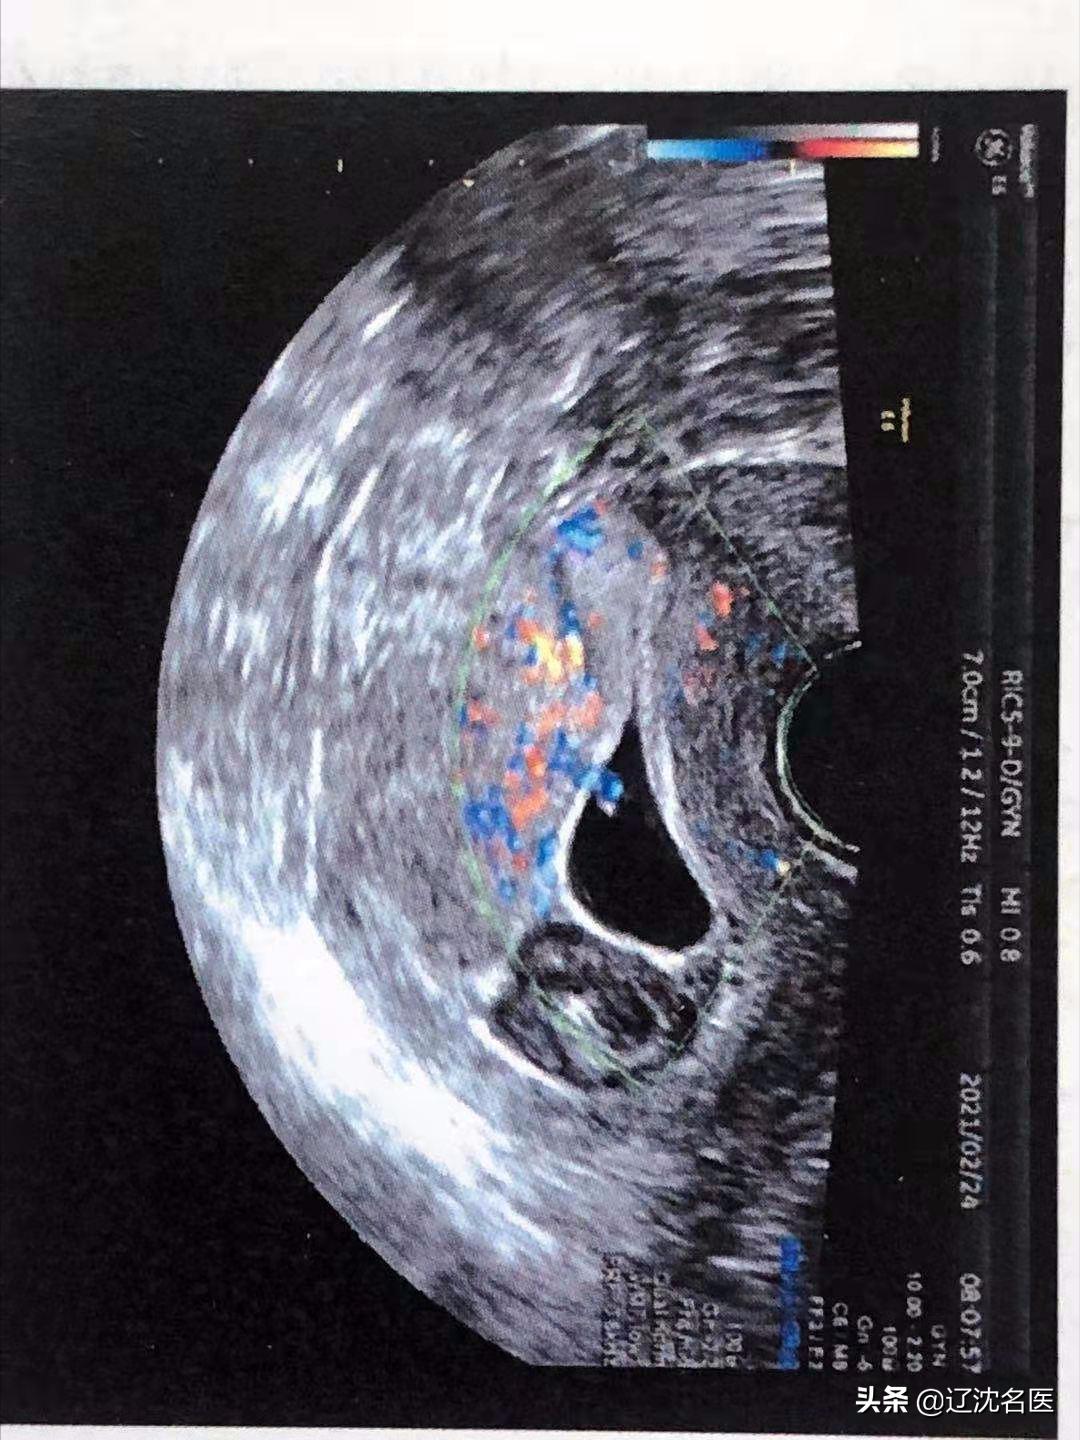

王华(化名)停经46天,伴阴道大量流血突然增多,下腹疼痛来省妇幼就诊。经急诊超声检查确认为剖宫产瘢痕部位妊娠,宫腔内还有很多积血,其妊娠囊生长在剖宫产切口憩室内,子宫前壁肌层仅剩不到1毫米,患者随时有子宫破裂大出血的危险。

辽宁省妇女儿童医院妇一科雷雨主任紧急接手,结合患者既往剖宫产2次,人工流产6次,考虑其盆腹腔黏连风险高,更进一步增大了手术风险。综合考虑后给予其制定了经阴道瘢痕妊娠病灶切除术,因该手术方式利用女性自然腔道,对腹壁各层无损伤,术中出血相对少,术后疼痛轻,恢复快,住院时间短,完全符合微创甚至无创以及加速康复外科理念。妇一科团队放弃休息时间,给患者进行了急诊手术,术中精细的分离解剖层次,确切的止血,顺利清除宫内妊娠组织并切除修补了剖宫产瘢痕憩室,手术仅持续了62分钟,出血量仅仅100毫升,结束妊娠同时切除病灶,避免了随时破裂大出血的危险,同时为再次妊娠提供较好的基础。